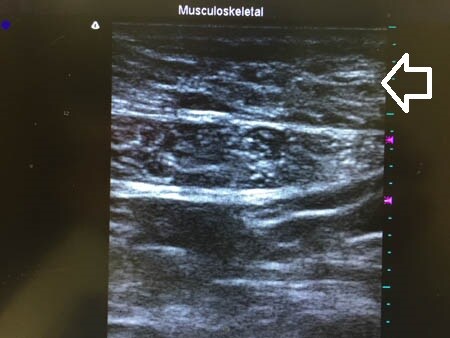

下腹部も同様に見てみましょう。

↓ ↓ ↓